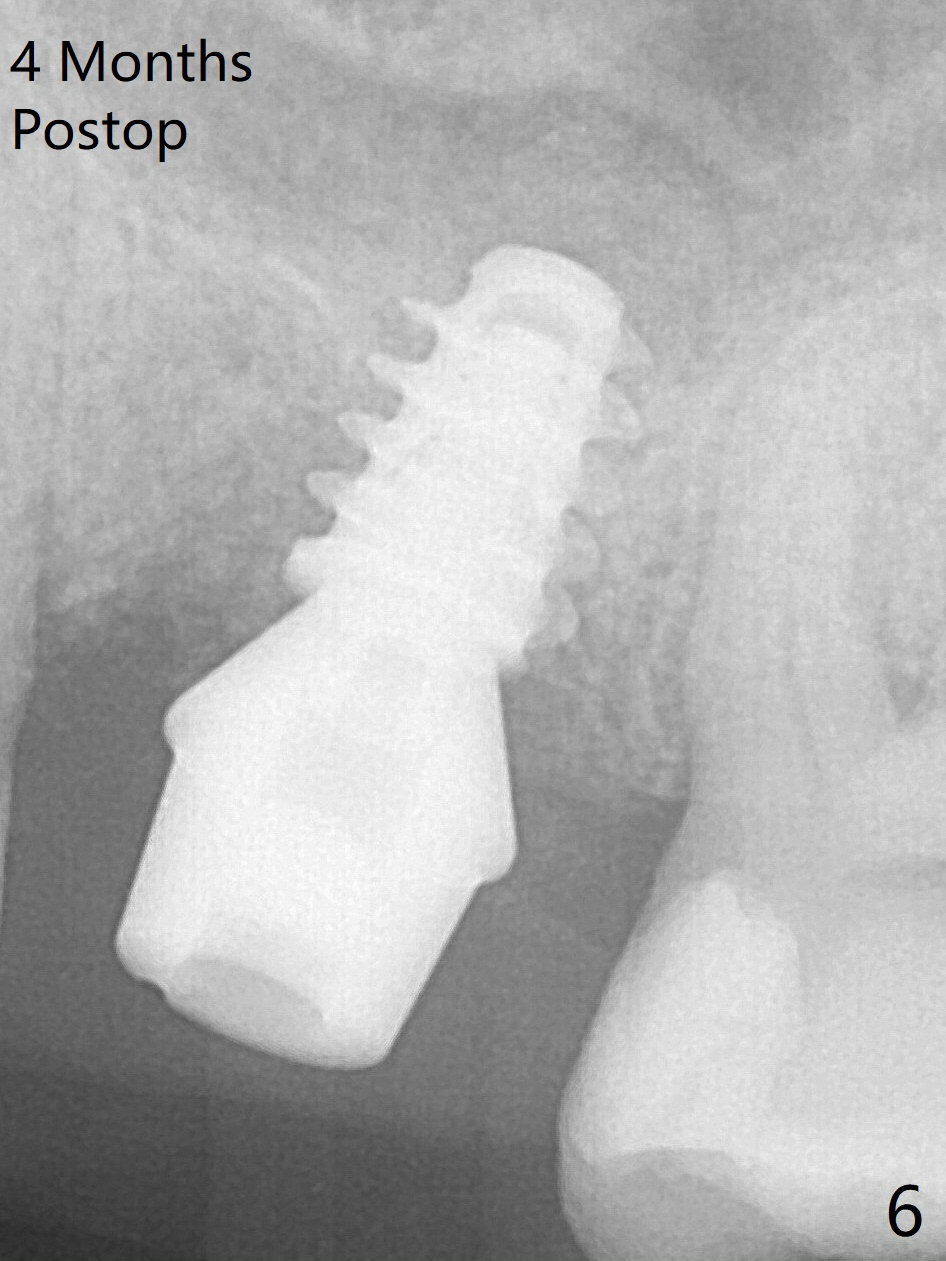

The implant is mobile 4 months postop (Fig.6). A 6x2 mm healing abutment is placed next. Although the implant remains mobile 6 months postop, the bone seems to have become denser around the implant (Fig.7-9). A healing screw is placed. When the bone height is limited (<7 mm), place a larger implant (>5.5 mm). The implant seems to have osteointegrated 8 months postop (Fig.10). Impression is taken following placing a 6.5x4(3) mm abutment. The patient reports pain after cementation, which is less when the abutment screw is loose (9.5 months postop, 2 weeks post cementation). CBCT taken after placement of a healing screw apparently shows loose bone mesial and distal to the implant (Fig.11 *). The implant trajectory is less favorable. It seems necessary to change to a large implant with more sold threads (Fig.12).